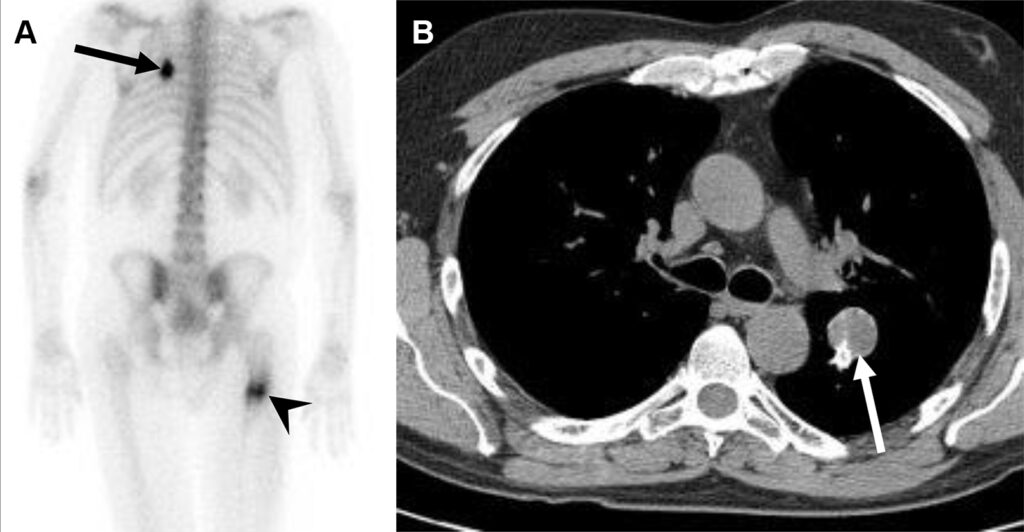

Metastasi da osteosarcoma in un uomo di 22 anni, a cui è stato recentemente diagnosticato un osteosarcoma del femore prossimale destro.

Oltre alla massiva e attesa ipercaptazione nella sede del tumore primitivo, lo studio whole-body rivela una captazione extra-ossea focale e intensa a livello dell’emitorace sinistro.

L’imaging morfologico conferma la presenza di un nodulo polmonare nel lobo superiore sinistro, caratterizzato da calcificazioni periferiche.

Le metastasi derivanti da tumori formanti osso, come l’osteosarcoma, mantengono la capacità osteogenica della lesione primaria. Esse producono matrice osteoide che calcifica, captando avidamente i radiotraccianti osteotropi (come il 99mTc-MDP) e rendendo le metastasi polmonari o dei tessuti molli ben visibili alla scintigrafia ossea.